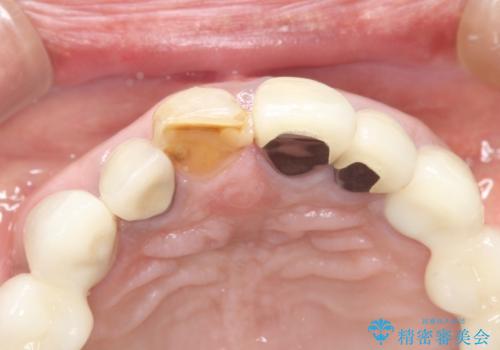

- 昔治療した前歯の色味が気になるとのことで来院されました。

昔に治療された前歯が変色しているのと、形態が自然ではありませんでした。

前歯2本をオールセラミックにすることにしました。